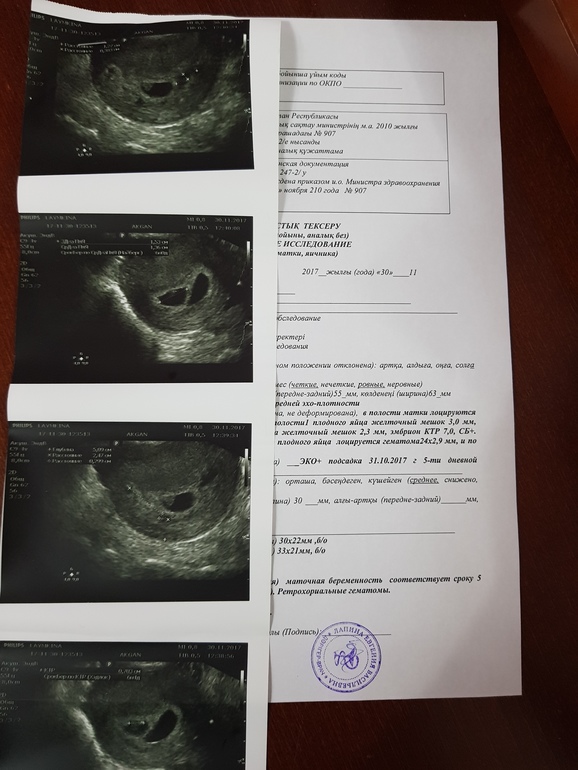

Анализы и процедуры. Помощь в расшифровке результатовДевочки Привет,были на повторном узи мы растем,пузожителей 2😊сб+,размерами одинаковые...разница только в ПЯ)))но на мои постоянные жалобы о мазне,Ре увидели 2 гематомы...выписка Ретрохориальные гематомы(((Ре назначила режим покоя,поддержку не отменила и теперь еще принимаю дицинон 3 р по 1....У кого как если были гематомы,как с ними прощались,а то я начиталась про это 😣😣😣